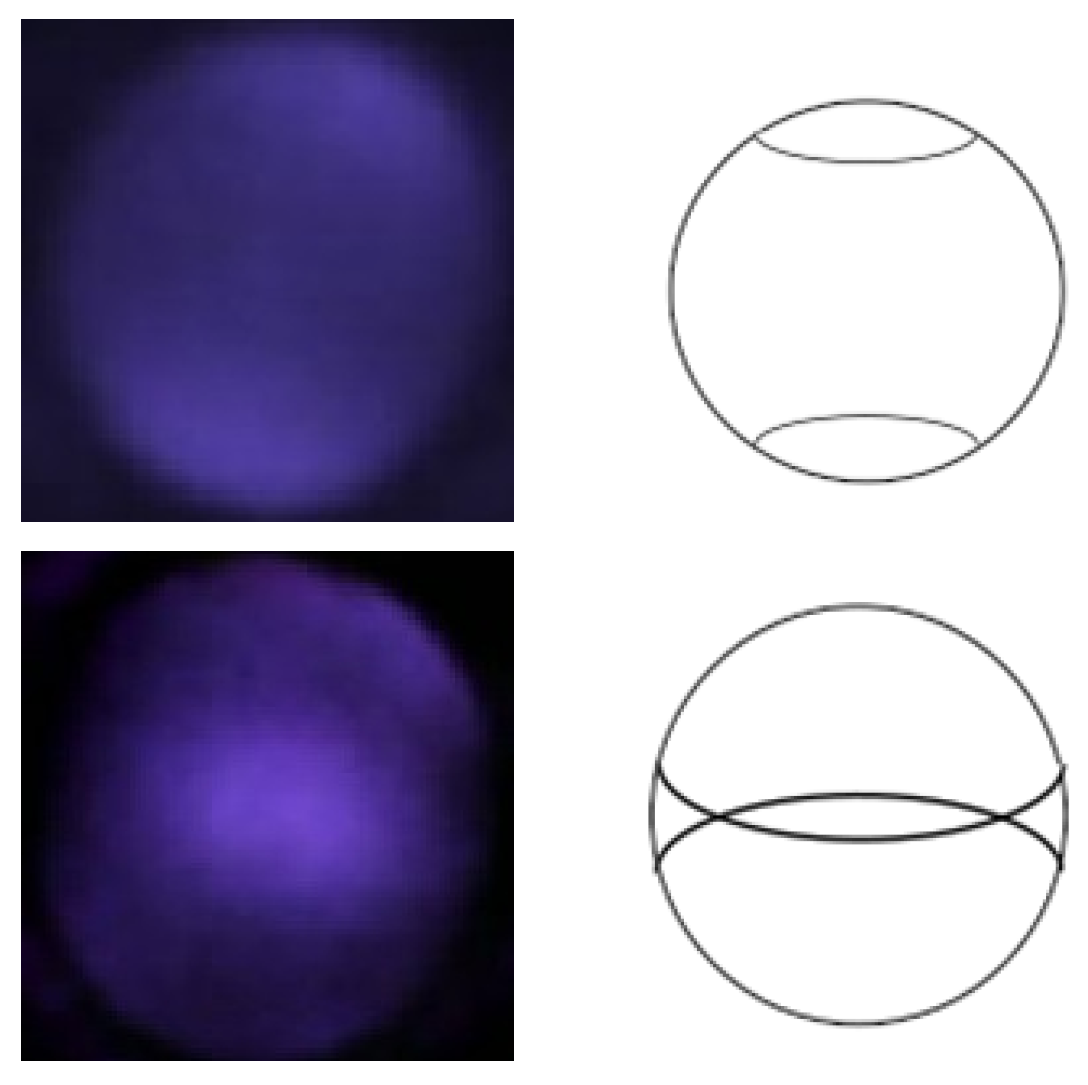

2.2. IR-Based Imaging with nun IR

2.3. Observation of Crescents

2.4. Grading Classification with CNN